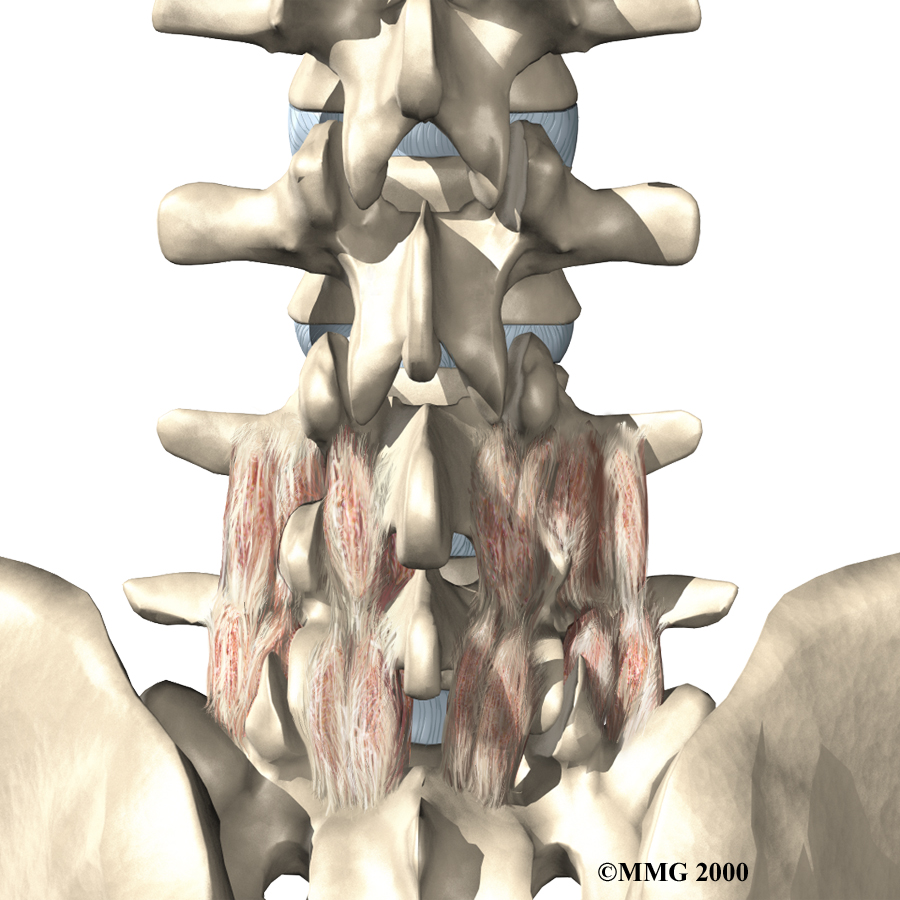

Between the vertebrae of each spinal segment are two facet joints. The facet joints are located on the back of the spinal column. There are two facet joints between each pair of vertebrae, one on each side of the spine. A facet joint is made of small, bony knobs that line up along the back of the spine. Where these knobs meet, they form a joint that connects the two vertebrae. The alignment of the facet joints of the lumbar spine allows freedom of movement as you bend forward and back.

Each segment in the spine has three main points of movement, the intervertebral disc and the two facet joints. Injury or problems in any one of these structures affects the other two. As a disc thins with aging and from daily wear and tear, the space between two spinal vertebrae shrinks. This causes the facet joints to press together.

The body responds to this extra pressure by developing bone spurs. As the spurs form around the edges of the facet joints, the joints become enlarged. This is called hypertrophy. Eventually, the joint surfaces become arthritic. When the articular cartilage degenerates, or wears away, the bone underneath is uncovered and rubs against bone. The joint becomes inflamed, swollen, and painful.

The physical therapists at FYZICAL San Francisco create a personalized program to help each patient regain back movement, strength, endurance, and function. Hands-on treatments such as massage and specialized forms of soft-tissue mobilization may be used initially. We use these treatments to help patients begin moving with less pain and greater ease.

Our physical therapist may also prescribe strengthening and aerobic exercises. Strengthening exercises focus on improving the strength and control of the back and abdominal muscles. Aerobic exercises are used to improve heart and lung health and increase endurance in the spinal muscles. Stationary biking offers a good aerobic treatment and keeps the spine bent slightly forward, a position that gives relief to many patients with lumbar facet joint arthritis.

We will show you how to improve strength and coordination in the abdominal and low back muscles. Our physical therapist will also evaluate your workstation and the way you use your body when you do your activities.